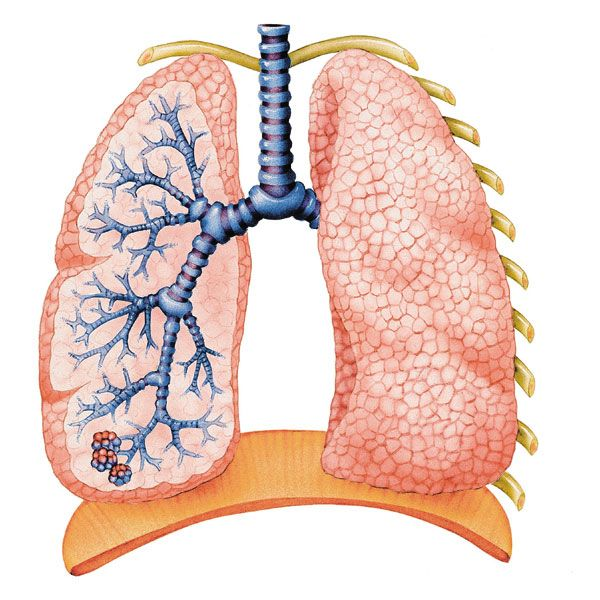

Alveoli are the sole site of gaseous exchange.

Alveoli are the sole site of gaseous exchange.

Alveoli

Tissue and function distribution in the human lungs

Requirements of human airways

- flexible

- divide many times, allow air to reach alveoli

- high elasticity (stretch & recoil)

- strong, to prevent collapse

Components

Trachea

- much of the wall is cartilage

- prevents collapse when air pressure is low

- Contains:

- elastic fibres: recoil & return

- smooth muscles: constrict airway

- blood vessels: supply cells with nutrients and remove waste

- Innermost lining is epithelium (ciliated and goblet cells)

Bronchi

- Same as trachea, just smaller

Bronchioles

- Larger ones may have some cartilage

- Mainly smooth muscle and elastic fibres

Alveoli

- Squamous epithelium

- elastic fibres: recoil after exhalation to prevent bursting